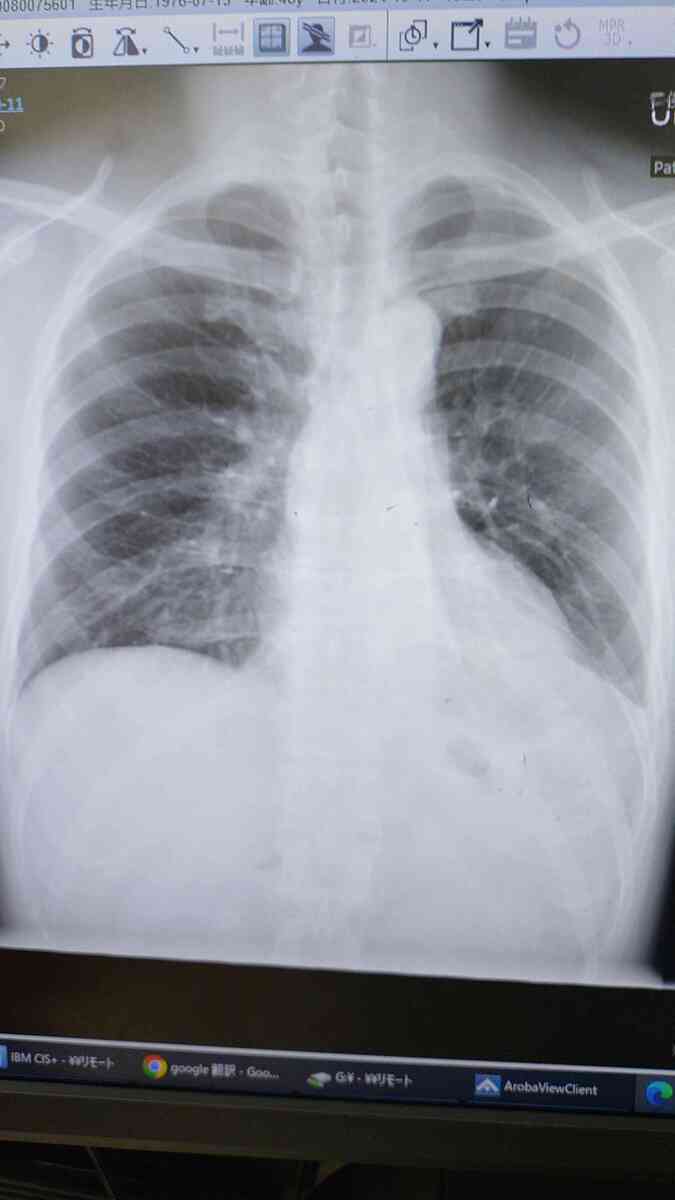

まずはコチラ、上は退院時で下は今日のワタシの肺です😀

上は左肺(写真では右側)の下に水が溜まっていて、右肺もやや萎んでいます。

下は左肺の水が無くなって右肺も大きくなっています☺️回復は時間がかかりましたが、軌道に乗って来ました